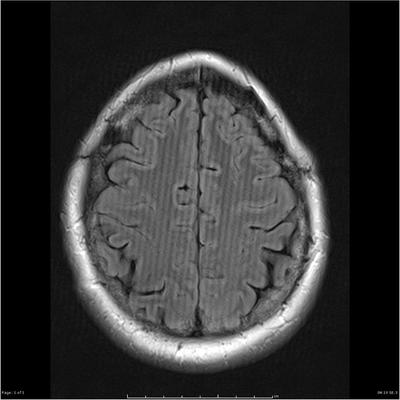

Figure 6 - 1 displays an example of what type of artifact?

Answer

• Aliasing

• Truncation

• Foldover

• Magnetic Susceptibility